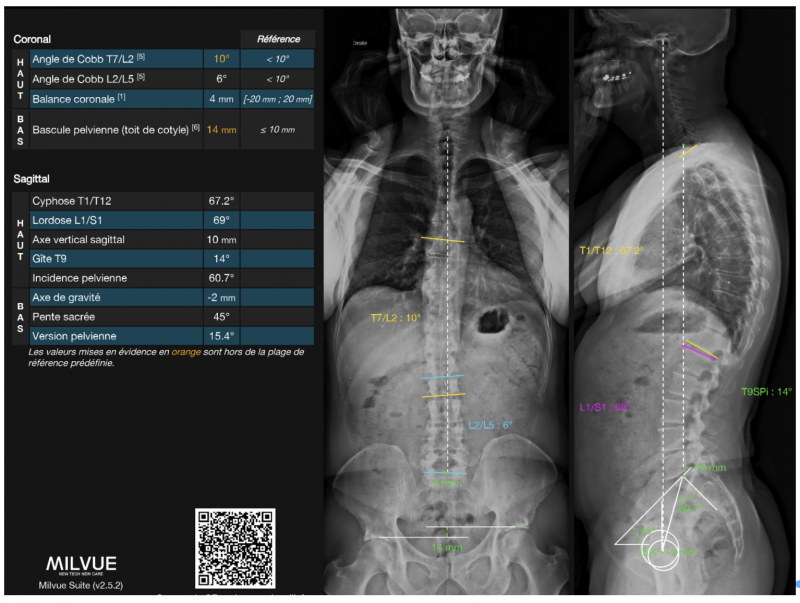

Au-delà de la question de la dose, la qualité géométrique est un autre atout majeur. L’orientation des faisceaux (orthogonaux entre eux et par rapport à la cible) évite les distorsions de projection. Les distances et les angles mesurés sur les clichés EOS sont directement exploitables : il n’est pas nécessaire de corriger les effets de magnification. La reconstruction 3D est toujours possible mais n’est pas systématique et nécessite une phase supplémentaire de post-traitement avec des outils dédiés, et n’est réalisée que dans certains cas particuliers, les reconstructions 2D étant généralement suffisantes dans la majorité des situations. L’aide d’outils d’intelligence artificielle a significativement simplifié la tâche du manipulateur, puisque les mesures automatiques ou semi-automatiques sont désormais accessibles avec la plupart des outils d’IA que les radiologues ont à disposition (mais impliquent un surcoût). L’IA permet également des mesures reproductibles, et rappelle systématiquement les normes angulaires pour chaque mesure, rendant l’analyse plus aisée pour tout le monde.

Figure 3: Exemple de mesures automatiques réalisées à l’aide d’un algorithme d’Intelligence Artificielle.

Figure 4: Exemple de livret résumé réalisé à l’aide d’un algorithme d’Intelligence Artificielle (correspondant aux mesures en Figure 3).